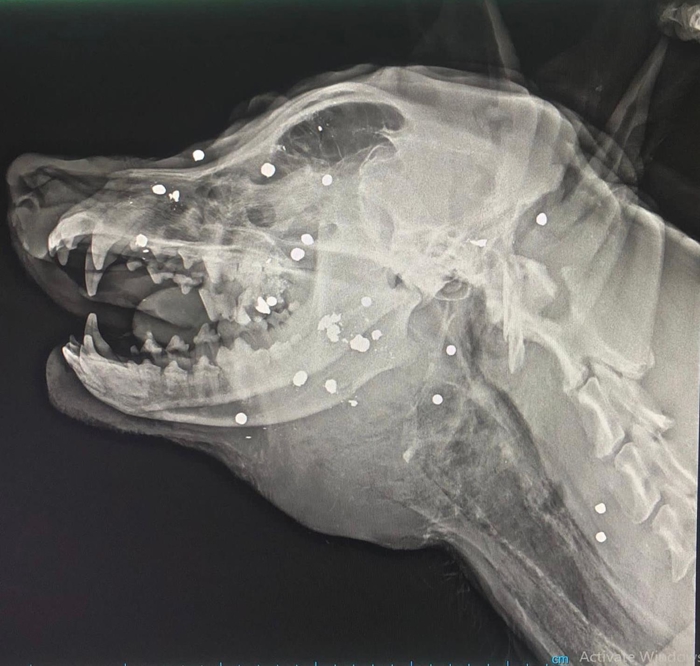

Olay, 5 Ağustos sabahı, Tekkeköy ilçesi Aşağıçinik Mahallesi'nde meydana geldi. Sosyal bilgiler öğretmeni Damla Özer, Rottweiler cinsi, 2 yaşındaki 'Haşin' adlı erkek köpeğini sokakta kanlar içinde buldu ve veteriner kliğine götürdü. Müdahale edilen ve çekilen röntgeninde av tüfeğiyle yakın mesafeden ateş edilip, vurulduğu anlaşılan köpek öldü. Şikayet ve suç duyurusu üzerine polisler, tüfeği ateşleyen kimliği belirsiz kişiyi bulmak için çalışma başlattı. 30'a yakın tüfek saçmasının başına isabet etmesi sonucu öldürülen köpeği için mezar hazırlayan Özer, şüphelinin bulunmasını ve en ağır cezayı almasını istedi.